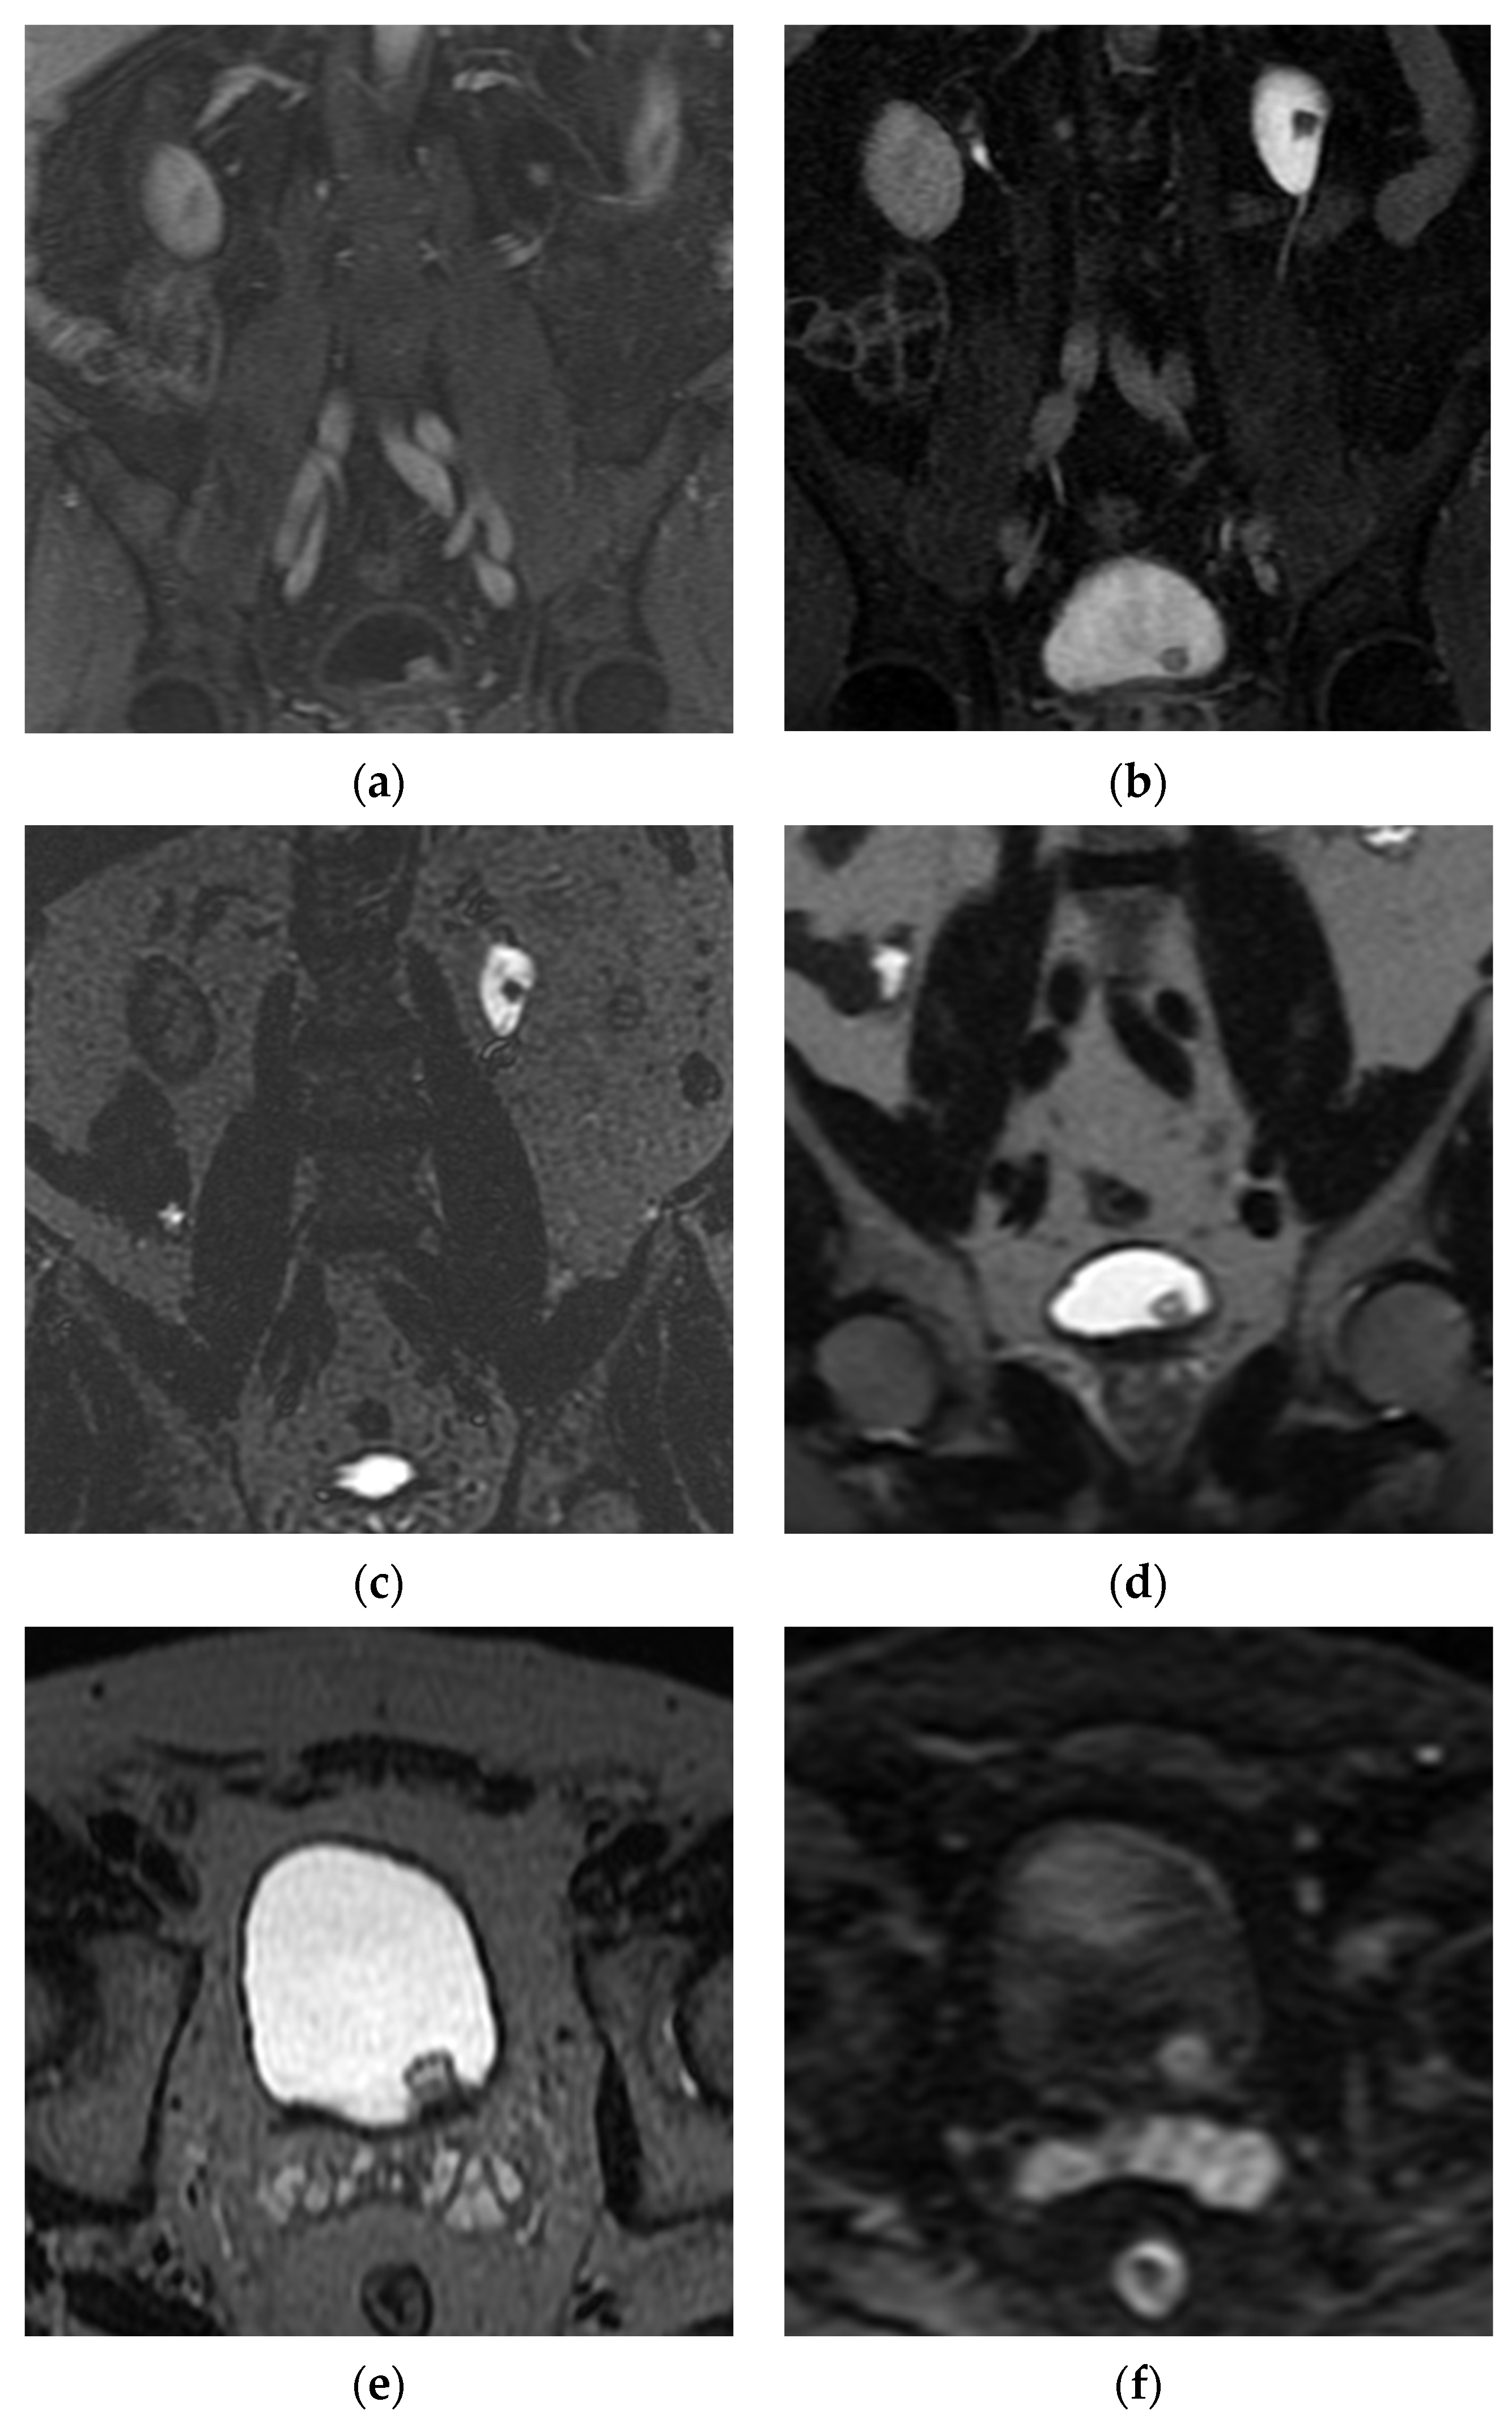

5.2. Magnetic Resonance Imaging (MRI)

- Pecoraro, M.; Takeuchi, M.; Vargas, H.A.; Muglia, V.F.; Cipollari, S.; Catalano, C.; Panebianco, V. Overview of VI-RADS in Bladder Cancer. AJR Am. J. Roentgenol. 2020, 214, 1259–1268. [Google Scholar] [CrossRef] [PubMed]

- Panebianco, V.; Narumi, Y.; Altun, E.; Bochner, B.H.; Efstathiou, J.A.; Hafeez, S.; Huddart, R.; Kennish, S.; Lerner, S.; Montironi, R.; et al. Multiparametric Magnetic Resonance Imaging for Bladder Cancer: Development of VI-RADS (Vesical Imaging-Reporting and Data System). Eur. Urol. 2018, 74, 294–306. [Google Scholar] [CrossRef] [PubMed]